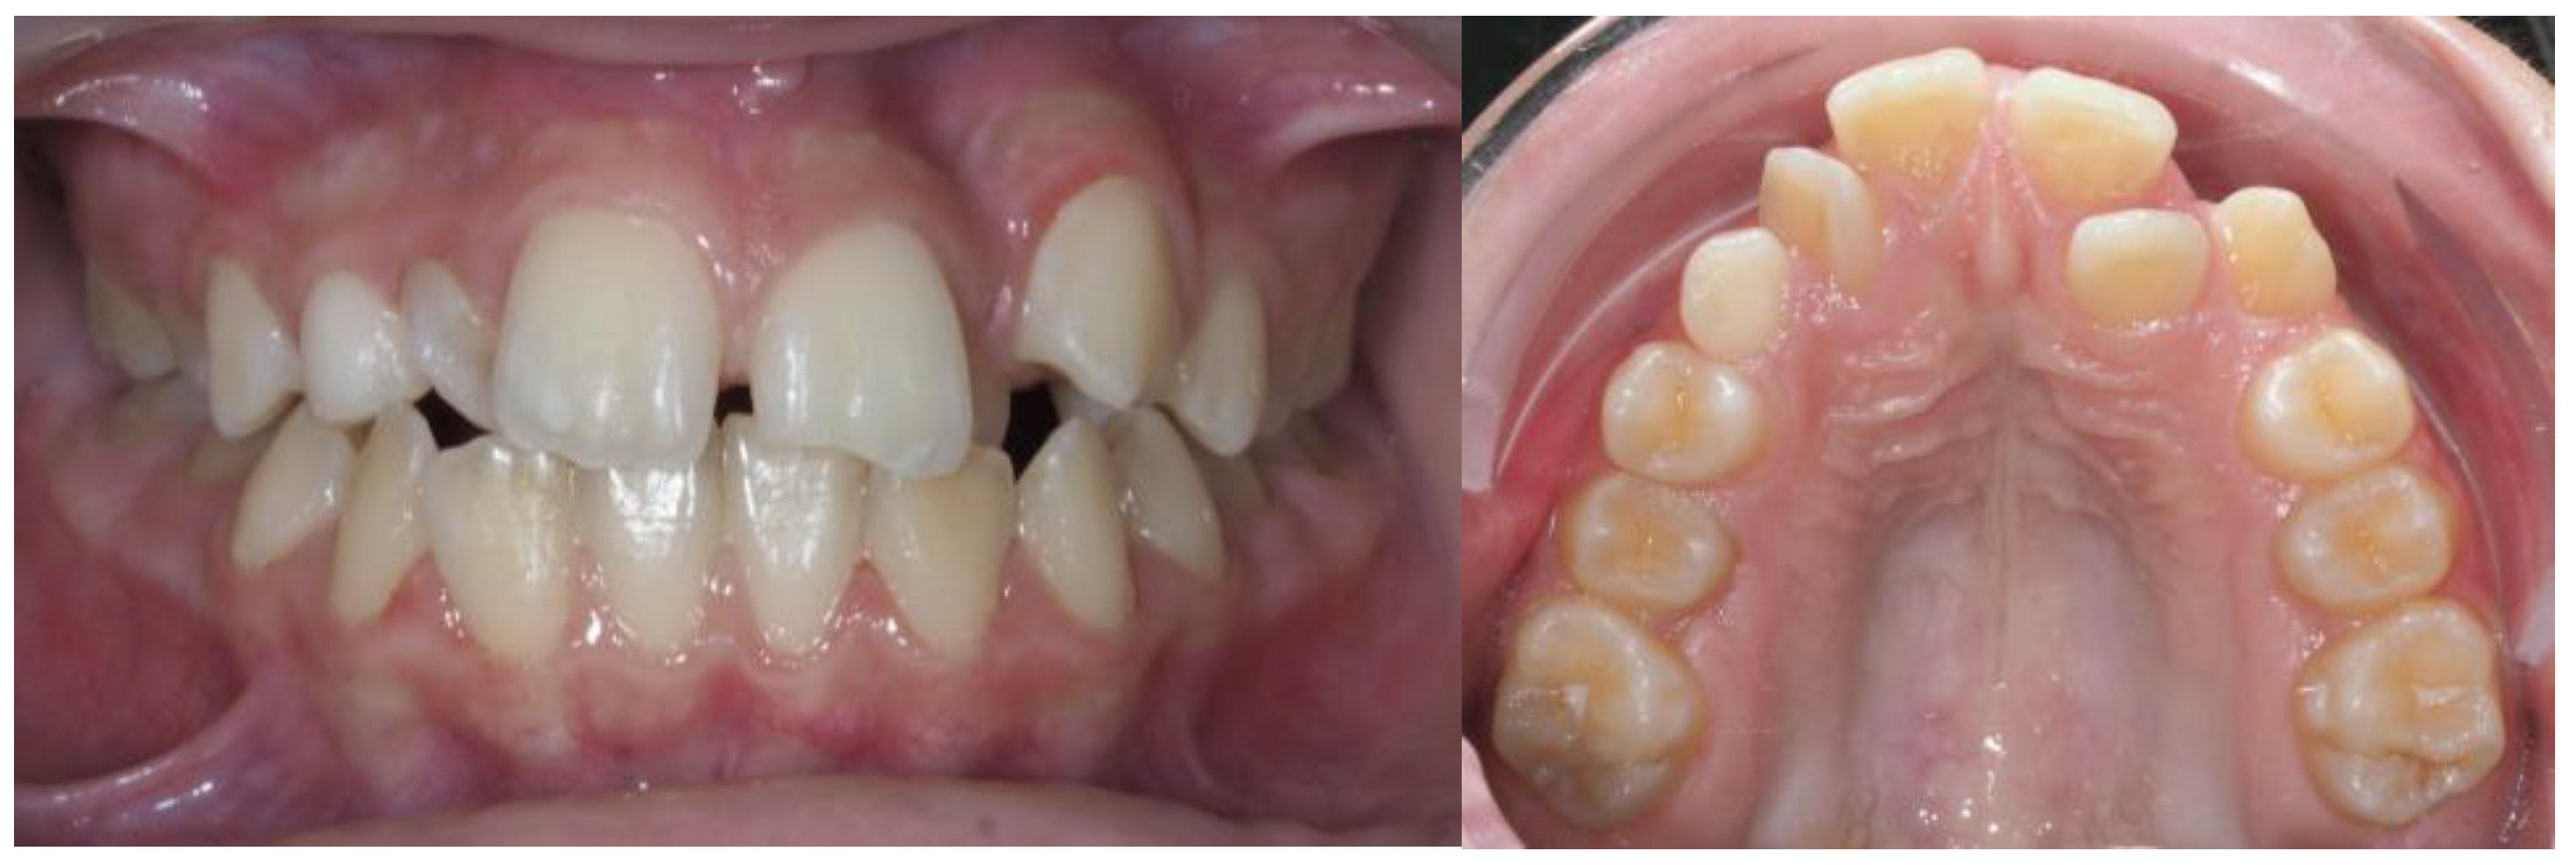

2.7. Clinical Case

| Pinho T., Amaral R. 2025 | ♀ 13 YO | Mx.C.I1 | C | R | V (impacted) | Cl I | Maintained | -Total root resorption of tooth #11 due to the position of the ectopic canine |

3.2. Clinical Case